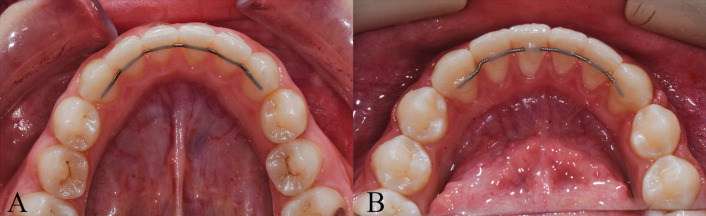

Methods: Fifty patients between the ages of 14.1 and 29.5 years were recruited for the study. The impact of 0.027x0.011-inch rectangular titanium dead-soft wire retainers was compared with that of 0.0215-inch six-stranded SS wire retainers. The retainers were bonded to the mandibular arch, and 3D models were evaluated after completion of the orthodontic treatment (T1), at the third month (T2), and at the sixth month (T3). Little's irregularity index (LII), the intercanine width, the pocket depth, the plaque index, bleeding on probing, and retainer survival were analyzed. The generalized linear model method was used to compare scores on LII, the intercanine width, the pocket depth, and plaque index values. Cochran's Q test was used to compare intragroup bleeding.